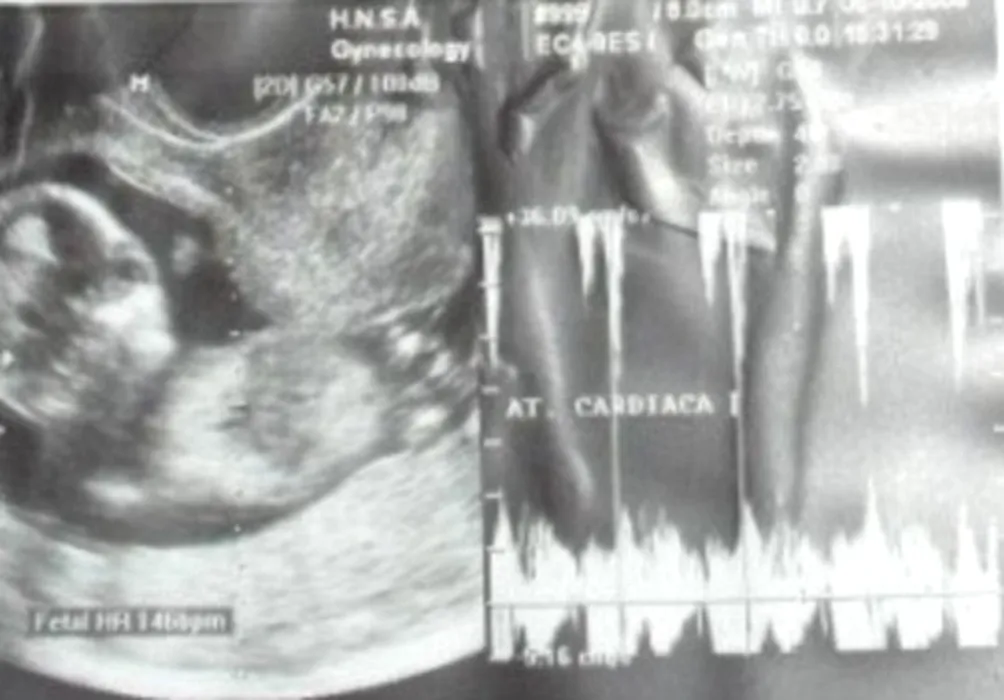

Ce surpriză a avut o gravidă când a făcut ecografie. „Semăna prea mult cu ea pentru a fi o coincidență”